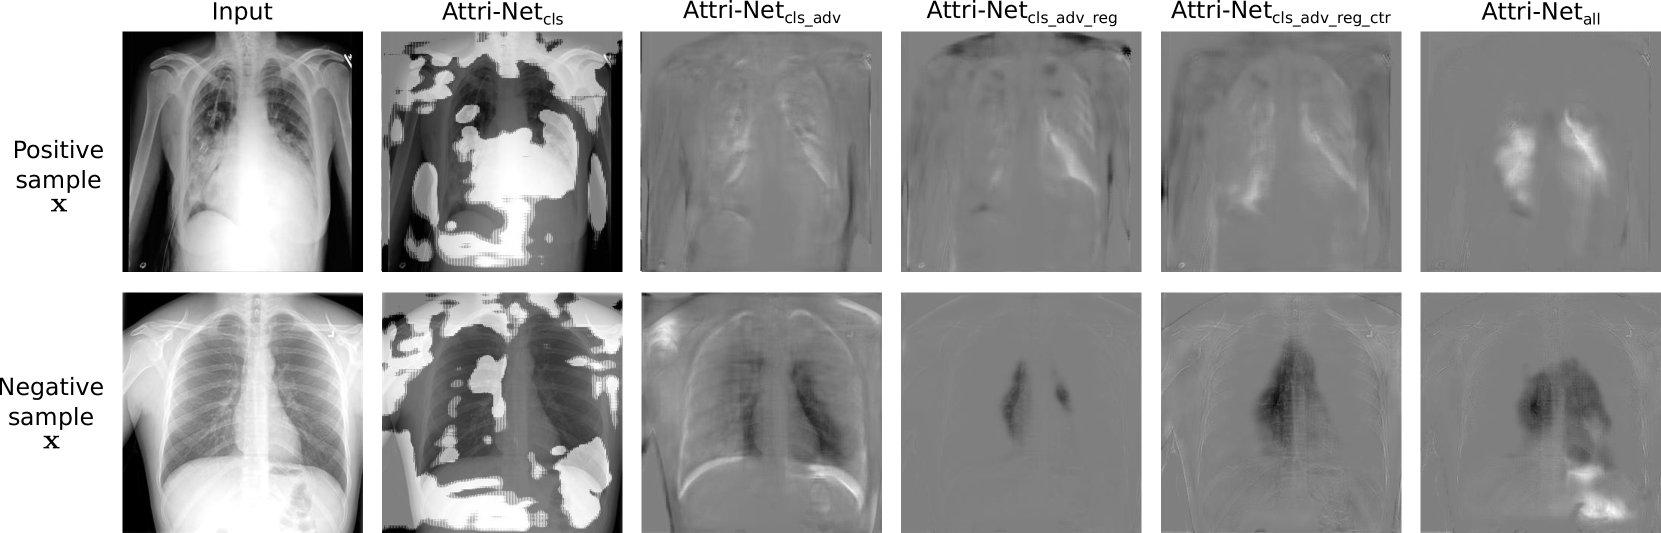

4.6 Ablation study

We performed an ablation study on the five loss terms for training the class attribution generator network described in Sec. 3. In Fig. 9, we show examples of attribution maps from our model trained with different losses, and in Table 4, we list the quantitative evaluation results of these models respectively.

We found that models trained with different losses perform similarly in classification AUC. However, the attribution maps visually change greatly, and the quantitative evaluation results of class sensitivity and disease sensitivity vary a lot. As shown in Fig. 9, after adding the adversarial loss term , the attribution maps focus on disease-relevant regions and become easy to understand. The regularization term encourages the attribution maps to be sparse. The addition of center loss improves the classification slightly but does not substantially affect the attribution maps. More importantly, the class centers provide a possible way to interpret Attri-Net globally. From Table 4, the model guidance loss greatly improves disease sensitivity, which is clearly shown from the attribution maps (last column) in Fig. 9.